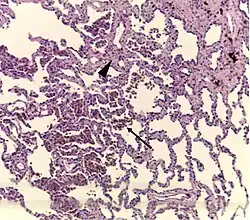

- Pathologic: Lung biopsy with "smoker's macrophages" limited to distal airspaces and peribronchiolar airspaces, and minimal to absent peribronchiolar interstitial fibrotic thickening

It is a histological finding, not a pathological description. When associated with disease, it is known as "Respiratory bronchiolitis-associated interstitial lung disease" or "RB-ILD".[4] Also, this disease is predominantly found in the upper lobe with centrilobar ground glass nodules. Importantly, no fibrosis is involved, just bronchial wall thickening. Treatment is to stop smoking.